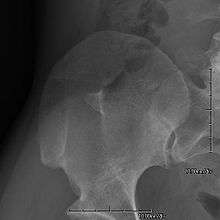

- Exostoses arising from the posterior aspect of the iliac bones ("iliac horns") are present in as many as 80% of patients; this finding is considered pathognomonic for the syndrome.

The hallmark features of this syndrome are poorly developed fingernails, toenails, and patellae (kneecaps). Sometimes, this disease causes the affected person to have either no thumbnails or a small piece of a thumbnail on the edge of the thumb. The lack of development, or complete absence of fingernails results from the loss of function mutations in the LMX1B gene. This mutation may cause a reduction in dorsalising signals, which then results in the failure to normally develop dorsal specific structures such as nails and patellae.[8] Other common abnormalities include elbow deformities, abnormally shaped pelvic (hip) bones, and kidney (renal) disease.